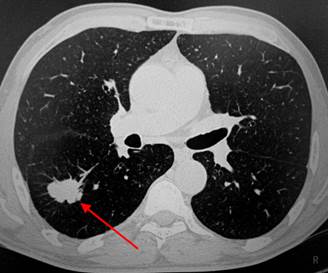

КТ снимок лёгких (Рак)

При МРТ печени можно увидеть нарушения кровотока, наличие опухолей в тканях, при КТ позвоночника легко определить структурные изменения в костной системе, защемления суставов и артерий. МРТ органов малого таза выявит причину кровотечений, нервные защемления, воспалительные процессы в сосудах. КТ легких укажет на опухоли, отобразит структуру и позволит определить природу затемнений.